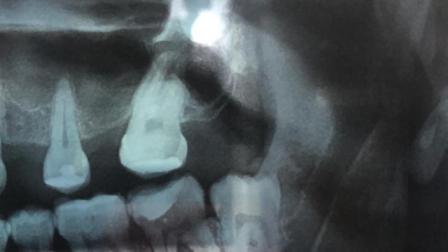

Aseguró que la terapia térmica (frío o calor) es recomendada cuando el diente se encuentra erupcionando en una buena posición, si existe un dolor agudo es imprescindible acudir con el dentista para que mediante radiografías logre diagnosticar si la erupción es adecuada o si es necesario llevar a cabo alguna cirugía bucal.